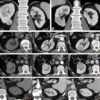

– Ung thư tế bào kị màu (Chromophobe renal cell carcinoma): chiếm tỷ lệ 5%, độ ác tính thấp, tiên lượng tốt nhất, khối u phát triển từ tế bào hình chêm (kẽ) ở biểu mô ống góp. Vi thể: có hai loại, một loại bao gồm các tế bào lớn, có bào tương dày, loại còn lại bao gồm các tế bào eosine. Các tế bào kị màu gồm 1 nhân trung tâm, đôi khi có rãnh sâu và một chất có nhiễm sắc dày có hạt nhân lớn, thường gặp là loại có 2 nhân. Cấu trúc mô học bao gồm các khối tế bào lớn, có ít chất đệm, các tế bào không chứa glycogen và lipid. Gel: có sự khuyết đoạn NST 7, đặc biệt là các NST 1,2,3.